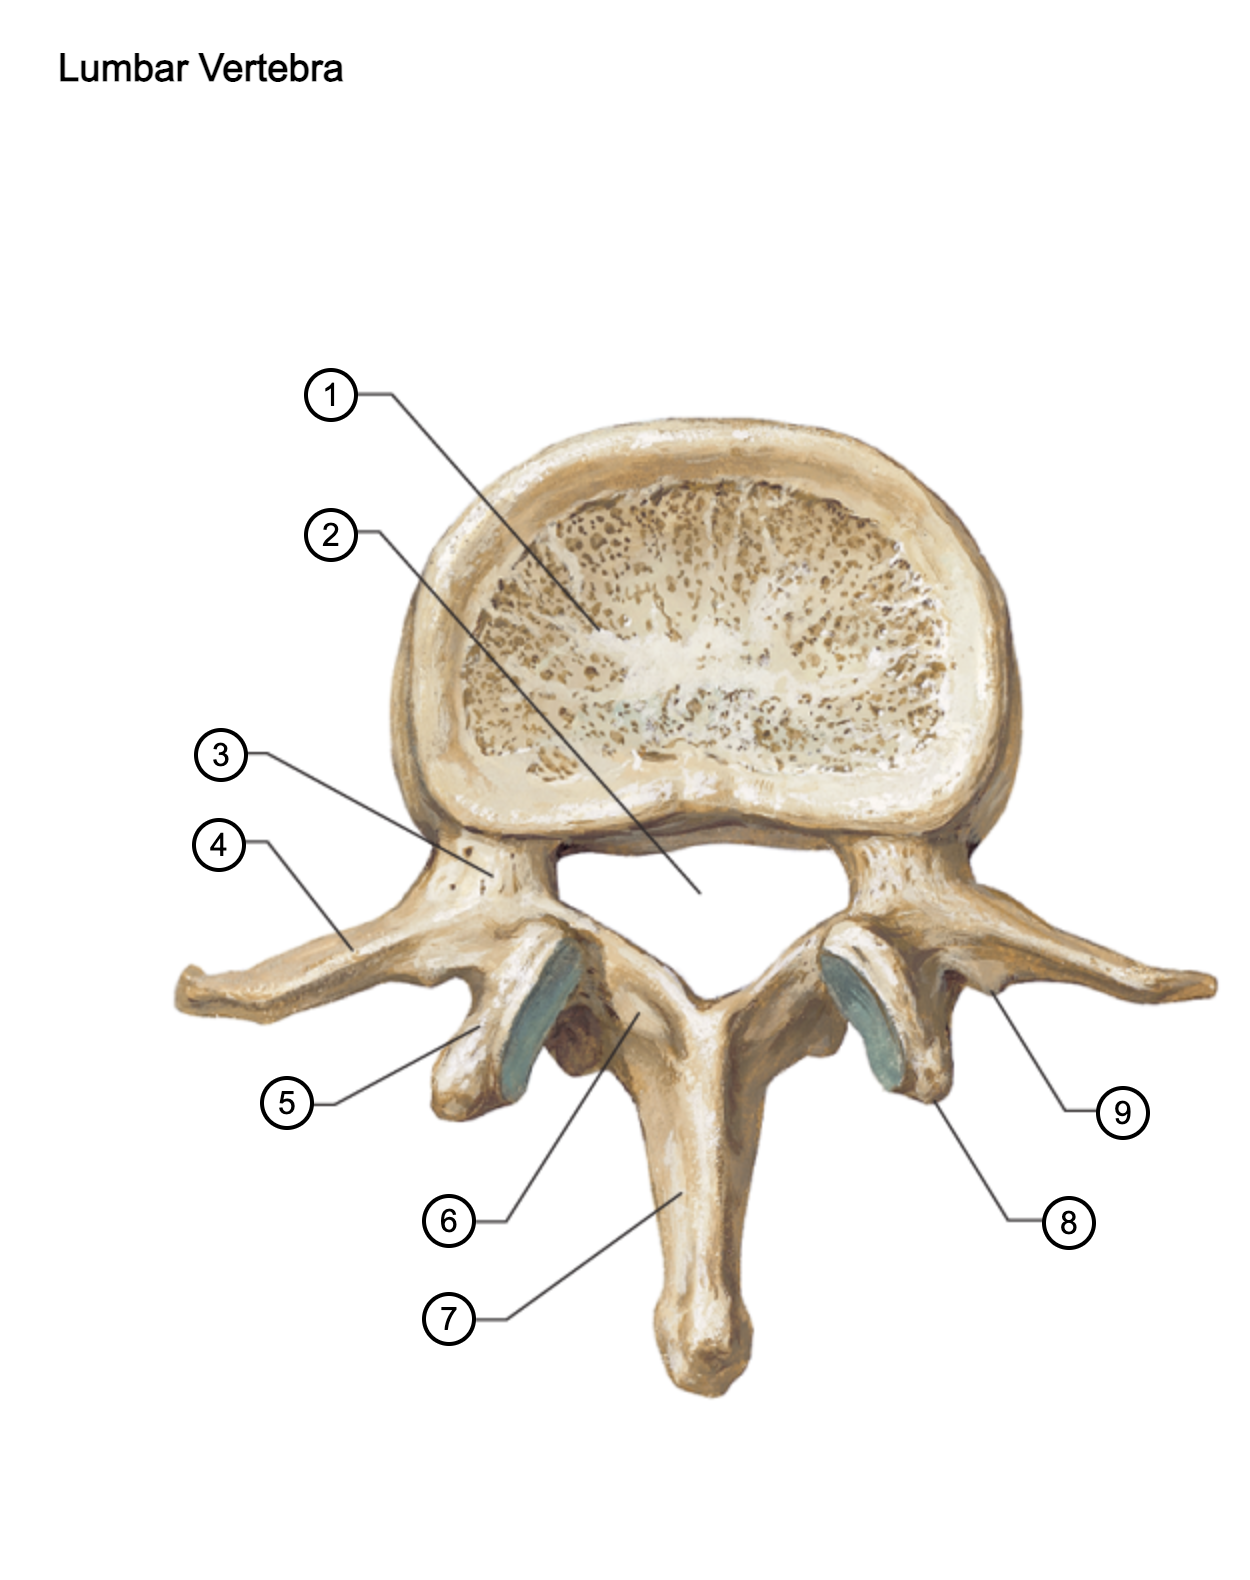

1

vertebral body

2

vertebral foramen

3

pedicle

4

transverse process

5

superior articular process

6

lamina

7

spinous process

8

mammillary process

9

accessory process